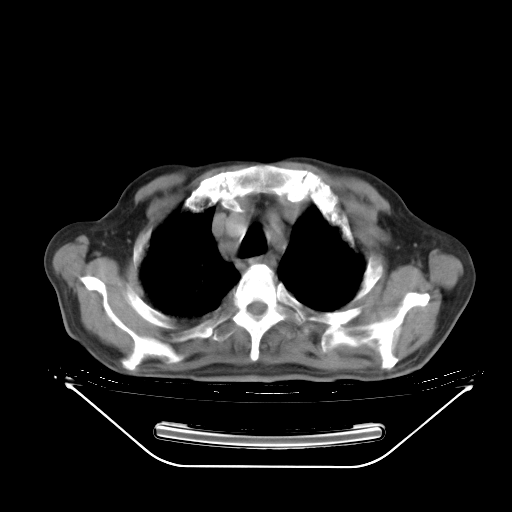

今天复查肺部CT,发现双肺广泛磨玻璃样改变。所以我把3月19日和5月9日相隔50天的肺部CT上传。请大家会诊。

2009年3月19日肺部CT片。

5月9日肺部CT(在4月27日齐鲁医院肺部CT描述部分肺组织磨玻璃样改变,12天后肺组织广泛磨玻璃样改变)

大致读了系列胸部CT:纵隔窗无明显异常,肺窗:从4、27至今:主要是双肺中下野外带可见毛玻璃样改变,目前处于急性肺泡炎阶段,至于原因考虑1、结替组织或胶原血管性疾病所致?2、恶性疾病如恶组在肺部所致的表现或细支气管肺泡癌?3、药物或其它原因如肺蛋白沉着症所致肺泡炎目前不太可能?总之,明天就去请我院的呼吸科、感染科、血液科和临免专家会诊哈。